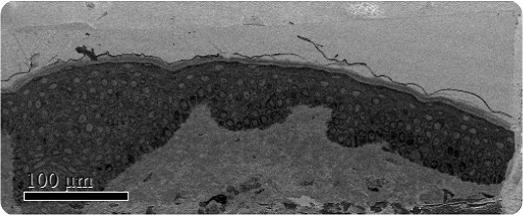

Melasma, a common dermalogical skin disease, involves the appearance of a dark skin discoloration on areas of the face upon sun exposure. The structural changes of melanocytes were studied by J.Y. Mun et al after subjecting them to Q-switched Nd:YAG laser exposure using SBFSEM (Figure 1). Melanocytes are present in the bottom epidermis layer and their dendrites can be found across all epidermis layers (Figure 2).

Low magnification SBFSEM image

Figure 1. Low magnification SBFSEM image displaying the entire block-face sample with a field of view of 200 x 500μm.